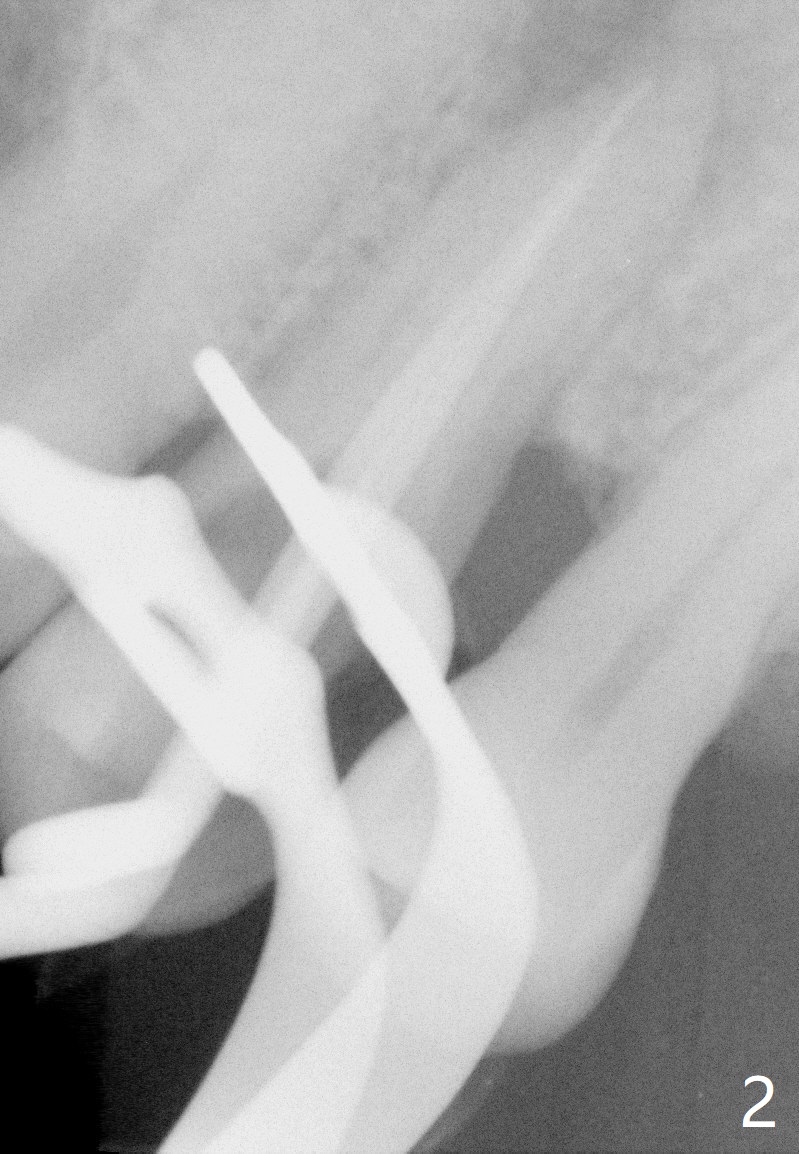

A 61-year-old man with chronic periodontitis presented to clinic for several implant placement (#3 10 14/15 18 30). For the tooth #12 (Fig.1), RCT was rendered (Fig.2). The tooth is non-salvageable 4.5 years post-treatment (Fig.3). Uneven bone loss mesiodistally makes implant placement challenging (Fig.4). A long implant will be used with ~3 mm subcrestal (mesially) and ~3 mm supracrestal (distally). A 3.5 or 4.0x13 mm implant will be placed subcrestal palatally and supracrestal buccally (Fig.5).